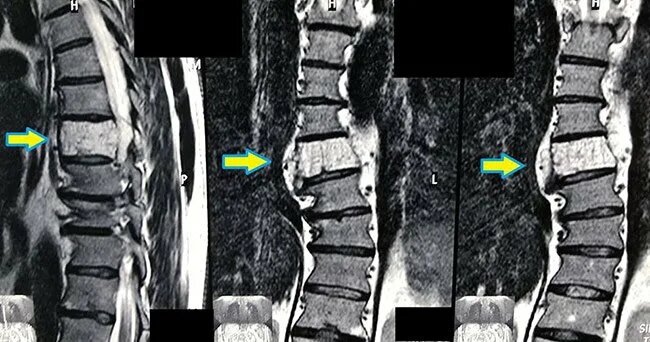

Гемангиома позвоночника — это доброкачественная опухоль, состоящая из сосудистой ткани. Чаще всего заболевание протекает бессимптомно и выявляется случайно при диагностике других патологий. Наиболее распространено среди людей среднего и старшего возраста, чаще встречается в грудном и поясничном отделах позвоночника.  Некоторые причины развития гемангиомы: Некоторые симптомы гемангиомы: Для диагностики магнитно-резонансную томографию (МРТ) Лечение гемангиомы зависит от ряда факторов, таких как размер опухоли, её расположение, наличие симптомов и общее состояние пациента. В большинстве случаев заболевание не вызывает серьёзных проблем и не требует вмешательства. Однако, если гемангиома вызывает болевой синдром или риски для здоровья, применяются различные методы терапии. Некоторые из них: При гемангиоме позвоночника противопоказаны массаж, физиотерапевтические и тепловые процедуры, так как они активируют кровоснабжение, что способствует росту новообразования.

Гемангиома позвоночника — это доброкачественная опухоль, состоящая из сосудистой ткани. Чаще всего заболевание протекает бессимптомно и выявляется случайно при диагностике других патологий. Наиболее распространено среди людей среднего и старшего возраста, чаще встречается в грудном и поясничном отделах позвоночника.

Для диагностики магнитно-резонансную томографию (МРТ)